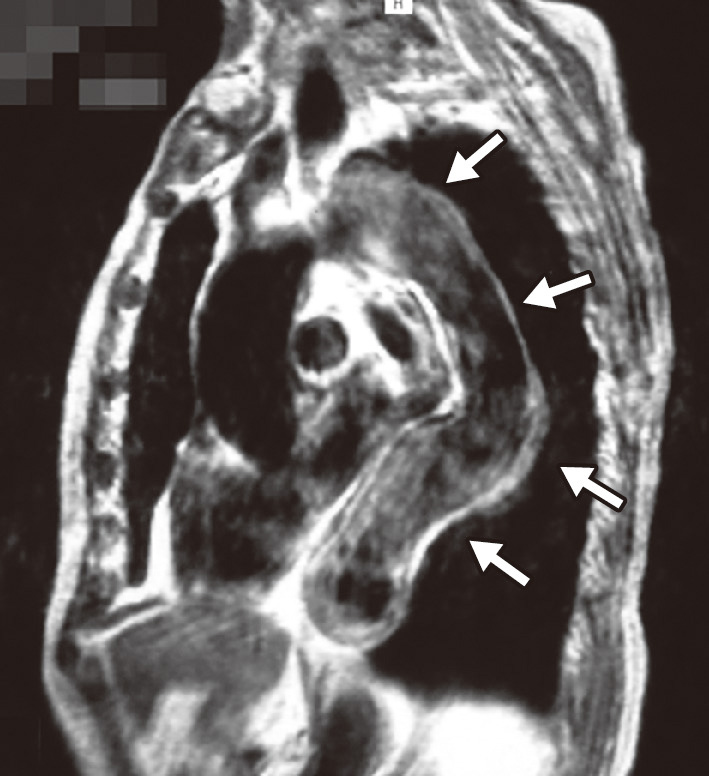

大動脈壁が脆弱化して局所的に全周性または一部が拡張した状態を大動脈瘤とよぶ.一般に,大動脈の外径の直径が正常部位の1.5倍 (目安として胸部大動脈系45 mm,腹部大動脈30 mm) をこえた状態を大動脈瘤と定義する.大部分は無症状のままに経過し,健診や医療機関受診の際の視診や触診,胸部X線写真正面像における縦隔拡大や側面像における拡大,腹部触診や腹部超音波 (図2) やCT (図3),MRI (図4) で発見され診断される.瘤の形状によって,紡錘状あるいは囊状,また壁構造の違いによって,瘤が内膜・中膜・外膜の3層すべてを有する真性動脈瘤と,中膜平滑筋層の連続性が失われ外膜や結合組織によって被包されている仮性大動脈瘤に分類される (図5).大動脈壁脆弱化の原因としては,外傷,梅毒,Marfan症候群などもあるが,最も大きな割合を占めるのは高血圧と加齢に伴う動脈硬化性変化であり,高齢男性に多い.大動脈瘤が解離したり破裂したりすると,激烈な胸背部痛や腹痛を訴えたり,血圧低下しショックに陥ったりする.いったんショック状態に陥った症例はもちろんのこと,病院に搬送されたとしても救命できる可能性は50%以下とされる.瘤径拡大スピードが高いほど,瘤形状が全体的でなく部分的であるほど,また当然,血圧が高いほど破裂リスクは高い.